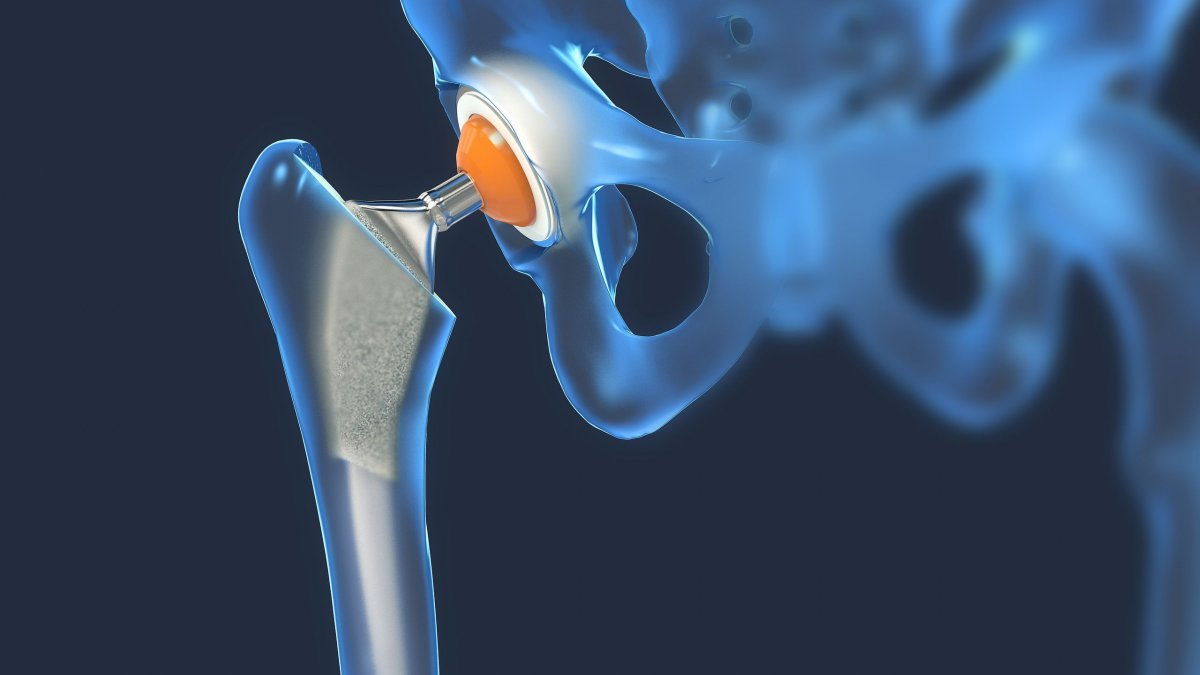

Οι επιστήμονες κρούουν το καμπανάκι του κινδύνου για τα κατάγματα ισχίου λόγω οστεοπόρωσης, καθώς όπως τονίζουν σε νέα τους μελέτη θα διπλασιαστούν έως το 2050.

Το κάταγμα του ισχίου εξαιτίας οστεοπόρωσης, το οποίο είναι ήδη ένα επικίνδυνο πρόβλημα για τους ηλικιωμένους σε όλο τον κόσμο, εκτιμάται ότι θα γίνει ακόμη σοβαρότερο για τη δημόσια υγεία στο μέλλον, σύμφωνα με μια νέα επιστημονική έρευνα που εκτιμά ότι έως το 2050 τα περιστατικά σχεδόν θα διπλασιασθούν διεθνώς, εν μέρει λόγω της προϊούσας γήρανσης του παγκόσμιου πληθυσμού.

Η συγκεκριμένη μελέτη, όπως μεταδίδει το Αθηναϊκό Πρακτορείο Ειδήσεων κρούει τον κώδωνα του κινδύνου για την ανάγκη καλύτερης πρόληψης και θεραπείας, ιδίως για τους άνδρες και τους πολύ ηλικιωμένους άνω των 85 ετών που κινδυνεύουν περισσότερο.

Η πιθανότητα ενός ατόμου να πάθει κάταγμα μετά τα 85 είναι υπερδιπλάσια σε σχέση με τις νεότερες ηλικιακές ομάδες.

Οι ερευνητές, με επικεφαλής τον αναπληρωτή καθηγητή Τσινγκ-λουνγκ Τσέουνγκ του Πανεπιστημίου του Χονγκ Κονγκ, οι οποίοι έκαναν τη σχετική ανακοίνωση σε συνέδριο της American Society of Bone and Mineral Research στο Τέξας των ΗΠΑ, ανέλυσαν στοιχεία από 19 χώρες για ανθρώπους άνω των 50 ετών που είχαν πάθει κάταγμα τα προηγούμενα χρόνια.

Εκτιμήθηκε ότι, με βάση τις υπάρχουσες τάσεις, θα πρέπει να αναμένεται αύξηση των καταγμάτων ισχίων σχεδόν σε όλες τις χώρες (18 από τις 19). Οι μεγαλύτερες μέσες ετήσιες αυξήσεις στα κατάγματα καταγράφηκαν στην Ολλανδία (2,1%) και στη Νότια Κορέα (1,2%).

Έως τα μέσα του αιώνα μας εκτιμάται σχεδόν διπλασιασμός τους σε σχέση με το 2018, με τους άνδρες να πλήττονται σε μεγαλύτερο ποσοστό έναντι των γυναικών.

Ολοένα μεγαλύτερο ποσοστό ανδρών να κινδυνεύει για κάταγμα ισχίου

Τα Ηνωμένα Έθνη προβλέπουν ότι το προσδόκιμο ζωής των ανδρών παγκοσμίως θα ξεπεράσει τα 75 έτη έως το 2050, με αποτέλεσμα ένα ολοένα μεγαλύτερο ποσοστό ανδρών να κινδυνεύει για κάταγμα ισχίου. Επιπλέον, εδώ και χρόνια η οστεοπόρωση υποδιαγιγνώσκεται και υποθεραπεύεται στους άνδρες.

Η μελέτη, σύμφωνα με τον δρ Τσέουνγκ, βρήκε ότι «η χρήση φαρμάκων κατά της οστεοπόρωσης μετά από κάταγμα ισχίου είναι χαμηλότερη στους άνδρες, σε σχέση με τις γυναίκες, κατά 30% έως 67%» (ανάλογα με τη χώρα). Η χρήση τέτοιων φαρμάκων μέσα στους επόμενους 12 μήνες μετά από κάταγμα ισχίου κυμαινόταν από 11% έως 50% (ανάλογα με τη χώρα).

Γι’ αυτό, ο Τσέουνγκ τόνισε ότι «περισσότερη προσοχή πρέπει να δοθεί στην πρόληψη και θεραπεία των καταγμάτων ισχίου στους άνδρες».

Οι ερευνητές επεσήμαναν ότι η μείωση στα κατάγματα που έχει παρατηρηθεί σε ορισμένες χώρες κατά τα τελευταία χρόνια (καθώς, μεταξύ άλλων, έχει γίνει ευρύτερα αντιληπτός ο κίνδυνος της οστεοπόρωσης), δεν αρκεί για να αντισταθμίσει την επίπτωση του αυξανόμενου και γηράσκοντος παγκόσμιου πληθυσμού, με συνέπεια τα κατάγματα ισχίου να εμφανίσουν ανοδική τάση μελλοντικά σε παγκόσμια κλίμακα.